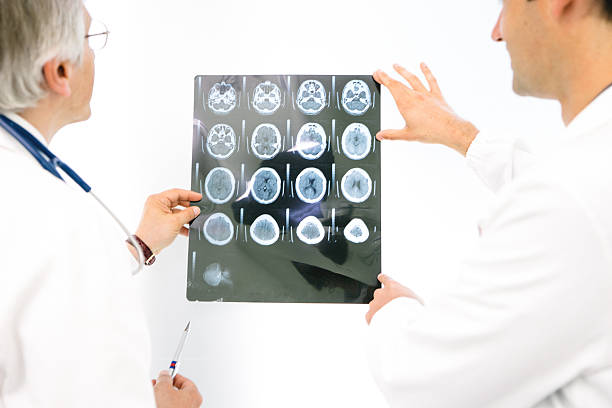

뇌출혈은 두 개 내에 출혈이 있어 생기는 모든 변화를 말하는 것으로 가장 큰 원인으로는 고혈압 증상을 지목하곤 합니다. 고혈압은 산소와 영양소가 뇌로 들어가는 통로인 혈관에서 변화를 일으키기 때문인데 뇌동맥류가 손상된 경우에도 발생할 수 있으며 잦은 흡연이나 음주 등 여러 원인으로 합병증으로 인해 발생할 수 있습니다. 특히, 뇌출혈 증상 발생시 가능한 빨리 병원으로 가야하고 약 2시간 안에 응급처치를 받아야 하는데 이는 응급처치를 받지 않으면 바로 뇌 손상으로 사망에 이를 수 있기 때문에 이번 시간에는 뇌출혈 전조증상에 대해 정리해 보겠습니다.